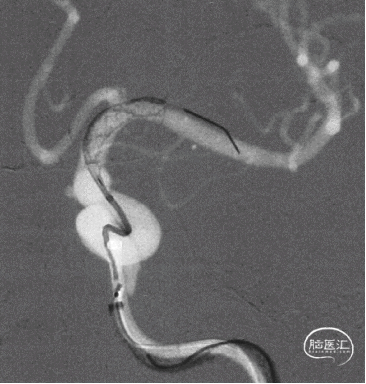

Fastrack微导管到位

TB Plus 4/35

3、释放TB Plus过程中,头端铆钉效果满意,释放过程顺滑。

4、通过微导丝按摩,可以使TB Plus贴壁效果更加。

5、FD植入后,动脉瘤明显造影剂瘀滞,效果显著。